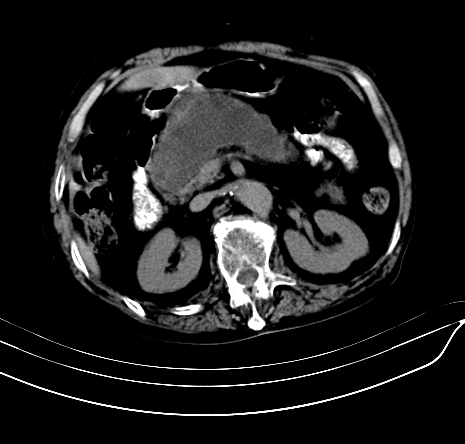

上腹部疼痛不适,行ct检查

胰腺明显肿大,密度减低,考虑慢性胰腺炎,假性囊肿形成不除外。

胰腺明显肿大,考虑慢性胰腺炎假性囊肿形成,不除外胰腺癌可能。

慢性胰腺炎,假囊肿形成,脂肪肝。